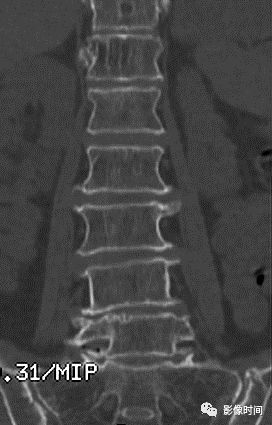

10栅栏征

栅栏征(The Palisade sign),也称灯芯绒椎体(corduroy vertebra)或灯芯绒征(corduroy sign)

脊椎椎体因病变导致骨小梁吸收、稀疏,为满足承重需要,存留的纵向骨小梁粗大;粗大骨小梁间以细条状密度减低区,形成栅栏样影像,故称栅栏征或灯芯绒椎体。

栅栏征最常见于血管瘤,以单个脊椎居多;骨质疏松如泛发性骨质增生症、老年性骨质疏松等亦可呈现此类表现,一般见于下胸椎、上部腰椎的多个椎体,只是伴有普遍的骨密度减低。有时自颈椎至腰椎全部椎体均出现栅栏征。栅栏征主要见于椎体。

典型病例

病例 1,脊柱血管瘤。胸腰椎 CT 冠状位、矢状位 MPR 重建示胸 12 椎体松质骨密度降低,其中可见粗大骨小梁呈栅栏状。

病例 2,67 岁女性,椎体血管瘤。腰椎侧位片示胸 12 及腰 3 椎体呈现栅栏征,磁共振检查证实为血管瘤。